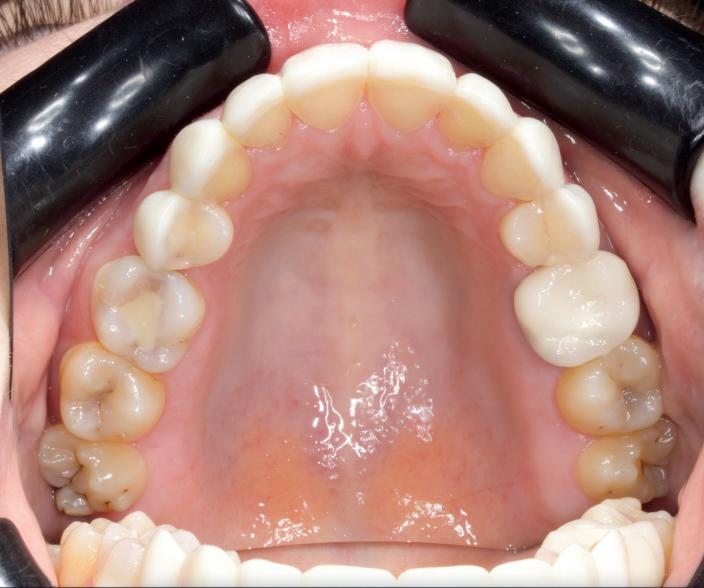

CASE STUDY

Guided implant approach for reproducible results, page 28

1. Adaptable to different guided surgery protocols: piloted, semi-guided or fully guided.

2. No friction between drills and guide sleeve, no overheating and no release of particles.

3. No specific drills and a very small surgical box.

4. Full control of drilling depth.

5. Your conventional driver-guided drilling sequence.